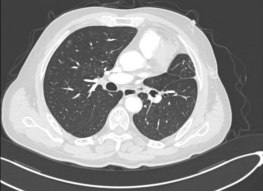

患者1为73岁男性,确诊中央型肺鳞癌(肿块大小约3.8cm),此前因化疗后出现消化道出血,无法耐受传统治疗方案。杨超教授团队创新性采用“介入灌注化疗+微创手术”联合方案,先通过介入治疗降低化疗副作用,再行左下肺癌根治术+左上肺支气管袖状切除术,成功为患者保留健康肺组织。术后病理检查证实切缘无癌残留,患者恢复良好,家属由衷感慨:“多家大医院建议全肺切除,没想到在这里保住了肺!”

另外两位患者中,患者2,61岁男性曾有传统手术经历,患者3,29岁女性为年轻早癌患者。杨超教授分析了两位患者的病情特点,最终决定为两人实施国内领先的Tubeless单孔胸腔镜楔形切除术(无气管插管、无尿管、无引流管)。术后61岁男性反馈格外积极,男性患者直言:“上次手术疼得不敢动,这次当天就能走路!”;年轻女性患者则表示:“像睡了一觉,醒来几乎不疼,隔天就顺利出院了”。